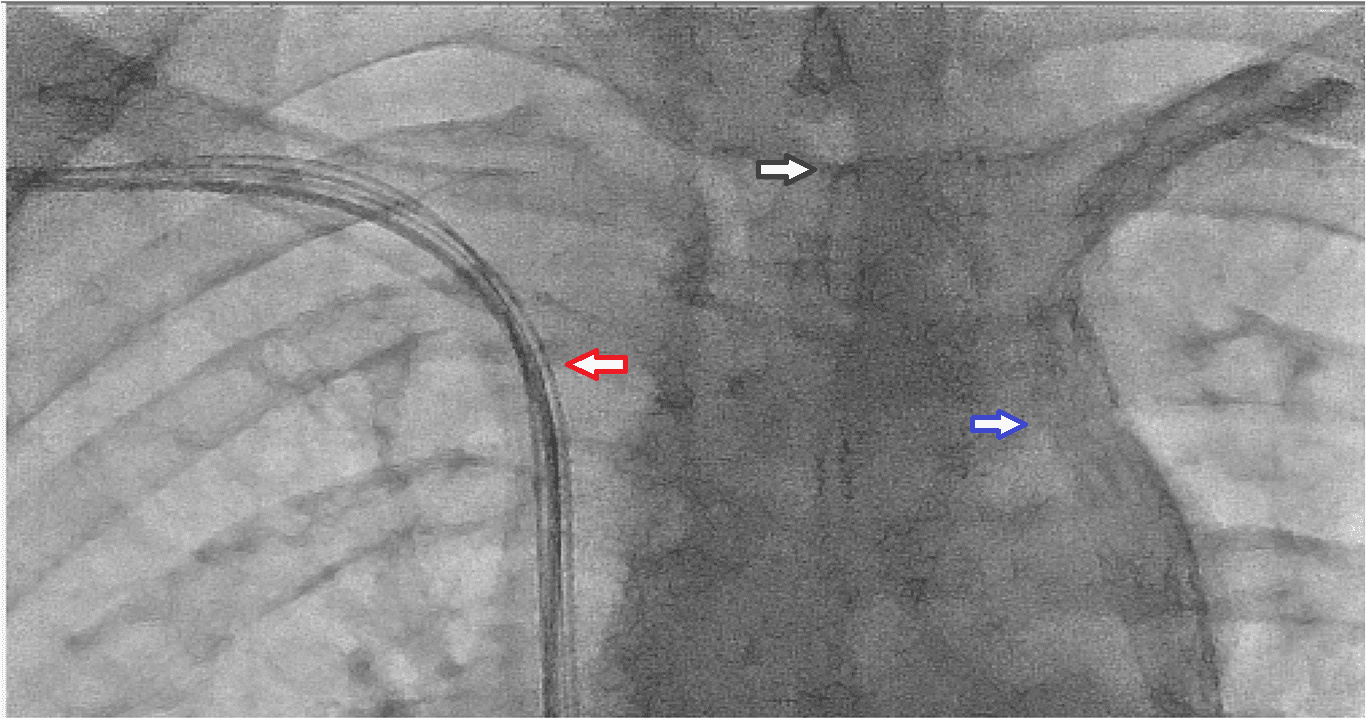

A 75 years old man with an ejection fraction of 35%, QRS duration 155 miliseconds and LBBB morphology on surface electrocardiogram was shedduled for CRT-D device implantation. Venography was performed as a part of our routine practice in order to explore the patency of the subclavian vein. After being sure about the patency of the vein, a pocket was created in the left pectoral region. The vein was canulated but the attempt to advance the guidewire has aborted. The tip of the guidewire fastened on a steep angle through the course of the vein. The venography was looked on again. Presence of a regressed innominate vein in a tapered aspect was noticed as well as a downward flow on the left side of the view . The patient had a PLVCS. Venography using the right antecubital vein showed the presence of a patent right SVC. A new pocket was created on the right pectoral region. Atrial, right ventricular and left ventricular leads were implanted using the right axillary vein puncture (Figure 1, 2). The procedure was quite straightforward and carried out succesfully (Figure 3).

Regression of the innominate vein in a tapered aspect caused us to overlook the presence of PLVCS. Venography from the right antecubital vein depicted the presence of right vena cava superior emptying in right atrium. Here the significant point to emphasize is that long phase venography is crucial in every case not to overlook PLVCS especially in the presence of a regressed innominate vein in a tapered aspect or a bridging innominate vein.